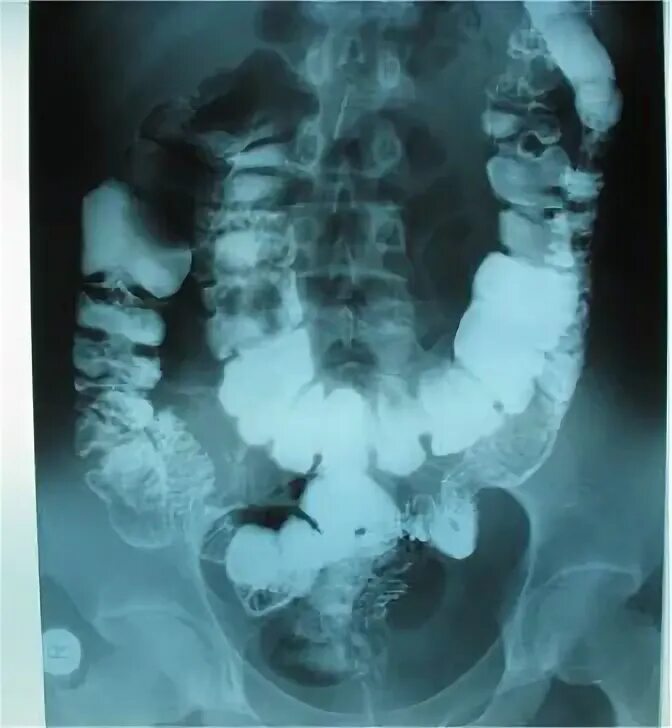

Долихоколон симптомы у взрослых